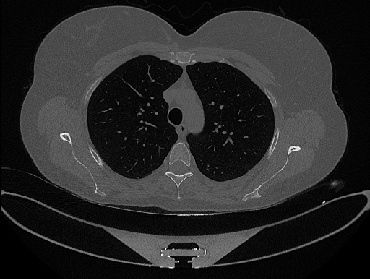

It should be mentioned that for explainability purposes [7, 8, 9], an anchor set was generated for the COV19-CT-DB database [5]. This included 11 anchors, each representing a respective 3-D CT scan obtained through an appropriate clustering procedure. Figure 2 shows a series of slices from a COVID-19 case, whereas Figure 3 shows a series of slices from a non COVID-19 case.